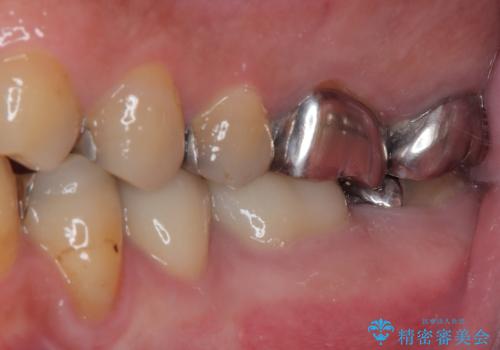

- 近医にてむし歯治療として根管治療を受けるも、痛みが全く改善しないとのことで来院された患者様です。

痛みが継続するため、「根管治療」と検索したところ、「ラバーダム」の重要性を知るところとなったようです。

根管治療を実施した後に、フルジルコニアクラウンにて補綴することとしました。

大臼歯の治療後に海外赴任され、数年ぶりに帰国されました。

奥歯に痛みがあるとのことで診察を行ったところ、海外(アメリカ)にて処置をした手前の歯が既に失活していることが分かりました。なお、治療を行った大臼歯はレントゲン写真上の治癒が認められました。

症状のあった歯に対しても根管治療を行い、同様に補綴治療を行いました。